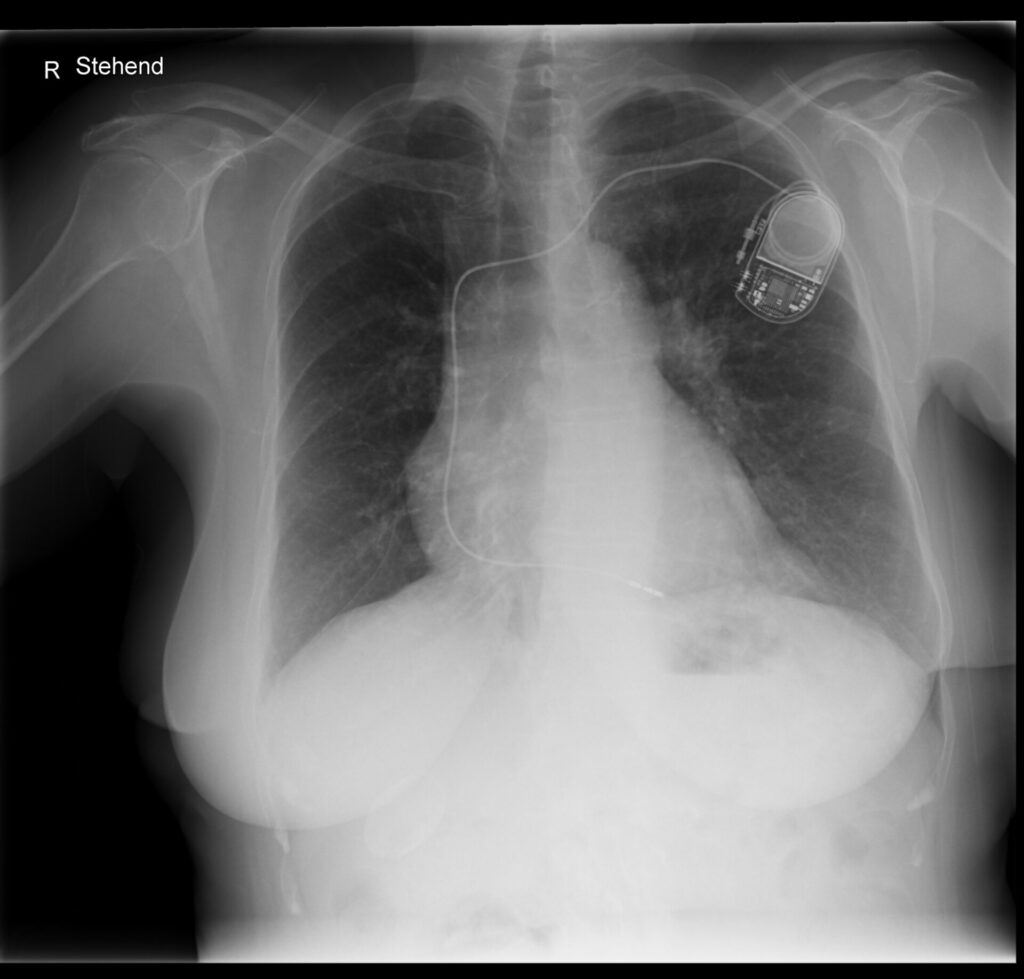

Radiologische Kontrolle von Herzschrittmachern und ICDs

Herzschrittmacher (SM) und implantierbare Cardioverter-Defibrillatoren (ICD) sind fester Bestandteil der Therapie von Herzrhythmusstörungen. Die Radiologie spielt dabei eine zentrale Rolle […]